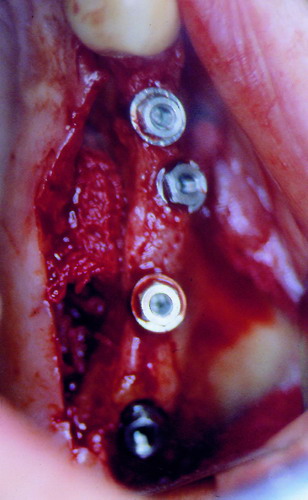

LA OCLUSIÓN MUTUAMENTE PROTEGIDA ES UN VIEJO CONCEPTO QUE CONSISTE EN LA MUTUA INTERACCIÓN DE LOS DISTINTOS GRUPOS DENTARIOS ENTRE SI. DE ESTA FORMA, LA TABLA PREMOLAR / MOLAR DE AMBOS HEMIMAXILARES ANTAGONISTAS, DETIENEN EL CIERRE MANDIBULAR EN CÉNTRICA, LOS CANINOS DISCLUYEN LAS PIEZAS POSTERIORES DURANTE LAS TRANSTRUSIONES, Y EL GRUPO INCISIVO LO MISMO DURANTE LAS PROPULSIVAS. SIN EMBARGO, DICHO CONCEPTO ES LIMITADO A LAS PIEZAS DENTARIAS, SIN TENER EN CONSIDERACIÓN LA IMPORTANTE FUNCIÓN QUE RECAE SOBRE LA ATM Y EN EL SOPORTE DE PRESIONES DURANTE ESTA DINÁMICA. ES ASI QUE EN EL AÑO 1981, EL DR. ANIBAL ALONSO GENERA EN LA CIUDAD DE BUENOS AIRES UN CONCEPTO MAS AMPLIO QUE DENOMINÓ : OCLUSION MUTUAMENTE COMPARTIDA. REF I EN EL QUE AMPLÍA EL CONCEPTO ANTERIOR, HACIENDO PARTÍCIPE A LA ATM EN LA MISMA. CUANDO EXISTE CARENCIA DE PIEZAS DENTARIAS POSTERIORES, YA SEA DE UN SOLO LADO O DE AMBOS , EL CIERRE MANDIBULAR ES DETENIDO POR LAS PIEZAS RESTANTE, FORZANDO A LA ATM A SOPORTAR PRESIONES MUY SUPERIORES A AQUELLAS PARA LAS QUE ESTA PREPARADA. FIG1 FIG2 FIG3 LUEGO DEL ESTUDIO CLÍNICO DE RIGOR, DONDE SE EVALÚA RADIOGRÁFICA Y PERIODONTALMENTE, SE PROCEDE A TOMAR MODELOS DE ESTUDIO Y MONTAR EN ARTICULADOR SEMIAJUSTABLE, SOBRE EL CUAL SE REALIZA UN ENCERADO PROGRESIVO DE DIAGNÓSTICO, A PARTIR DEL CUAL SE CONFECCIONA UN JUEGO COMPLETO DE PROVISIONALES DE AMBAS ARCADAS , INCLUYENDO LAS PIEZAS FALTANTES. SE ABORDA EL CASO YA QUIRÚRGICAMENTE DONDE EN UNA PRIMERA ETAPA SE TALLAN PRIMARIAMENTE LAS PIEZAS DENTARIAS Y SE PROCEDE, EXODONCIANDO EL INCISIVO CENTRAL SUPERIOR DERECHO, A REALIZAR UNA ROG(REGENERACIÓN ÓSEA GUIADA), PARA INMEDIATAMENTE INSTALAR PARTE DE NUESTROS PROVISORIOS EN LA GUIA ANTERIOR. SE ADAPTAN A LOS SECTORES POSTERIORES LAS PRÓTESIS REMOVIBLES QUE PORTABA, Y SE ESPERAN CUATRO MESES, AL CABO DE LOS CUALES SE REALIZA UN ESTUDIO CON DENTASCAN, MEDIANTE EL USO DE UNA FÉRULA RADIOLÓGICA CON TUBOS METÁLICOS , QUE NOS SERVIRÁ TAMBIÉN DE GUÍA QUIRÚRGICA. PROCEDEMOS ENTONCES A LA IMPLANTACIÓN DE LOS SECTORES EDÉNTULOS MEDIANTE IMPLANTES ROSCADOS Y TÉCNICA SEMI SUMERGIDA. TRANSCURRIDAS OCHO SEMANAS OBSERVAMOS UNA CORRECTA SALUD PERIMPLANTARIA, Y REALIZAMOS LA INSTALACIÓN DE LOS ABUTTMENTS ALCANZAMOS ENTONCES EL PUNTO EXACTO DONDE DEBEREMOS COMENZAR A RECONTRUIR EN FORMA PERMANENTE. PAZ DEL SISTEMA: CENTRICIDADARTICULAR-PAZ MUSCULAR-ESTABILIDAD- -ACOPLAMIENTO. BASES FUNDAMENTALES DE LA OCLUSIÓN ORGÁNICA FIG41 FIG42 PROCEDEMOS NUEVAMENTE A TOMAR IMPRESIONES, EN ESTE CASO DEFINITIVAS , MONTAR NUEVAMENTE EN ARTICULADOR, Y CONSTRUIR LAS RESTAURACIONES PERIFÉRICAS TOTALES EN BASE A PORCELANA SOBRE ORO GALVANIZADO. REF. II SOBRE LAS MISMAS TERMINADAS Y YA EN BOCA, CHEQUEÁMOS TODOS LOS ELEMENTOS QUE CONSTITUYEN UNA REHABILITACIÓN ORAL INTEGRAL, DESDE LA SALUD ENDODONTICA DE PIEZAS TRATADAS O NO, LA SALUD PERIODONTAL, EL AJUSTE PERIFÉRICO DE LAS RESTAURACIONES, LA ESTABILIDAD EN LA ATM, Y LAS FUNCIONES OCLUSALES, CHEQUEOS ESTOS QUE SE REPETIRAN EN CADA UNO DE LOS CONTROLES POST OPERATORIOS. FIG46 FIG47 FIG48 FIG66 FIG67 REFERENCIAS: REF I: OCLUSIÓN Y DIAGNÓSTICO EN REHABILITACIÓN ORAL REF. II ELECTROFORMACIÓN EN ODONTOLOGÍA RESTAURADORA.